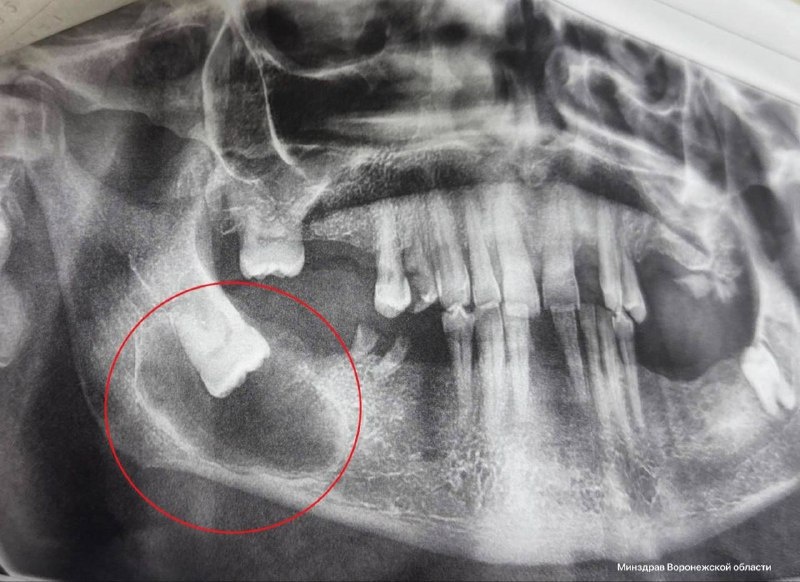

Житель Воронежа обратился за помощью из-за боли и асимметрии лица

Обследование выявило неправильно растущий зуб, вызвавший кисту и разрушение кости. Хирург Анастасия Асеева выполнила успешную операцию по удалению зуба и очищению раны. Пациент быстро восстановился и был выписан из клиники. Врачи подчеркивают важность раннего выявления патологий зубов мудрости, способных незаметно разрушать костную ткань.